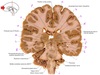

1

Q

a

body of corpus callosum

2

b

Anterior horn of lateral ventricle

3

c

Septum pellucidum

4

d

Rostrum of corpus callosum

5

e

Head of caudate nucleus

6

f

Anterior limb of internal capsule

7

g

Putamen

8

h